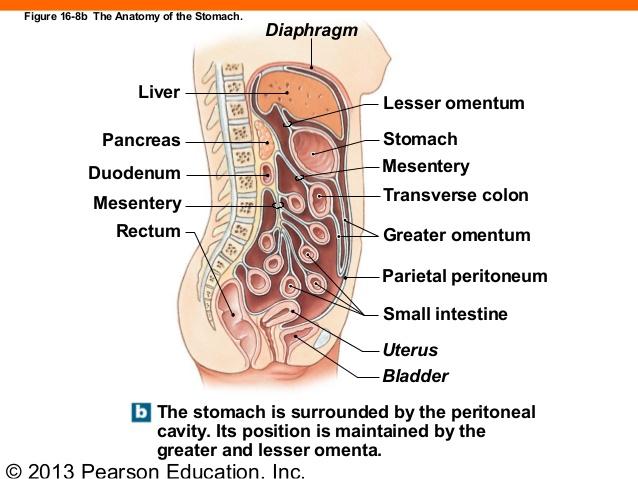

Serous membranes

...

2

Parietal Peritoneum

3

Dorsal Mesentery

Lesser Omentum

Greater Omentum